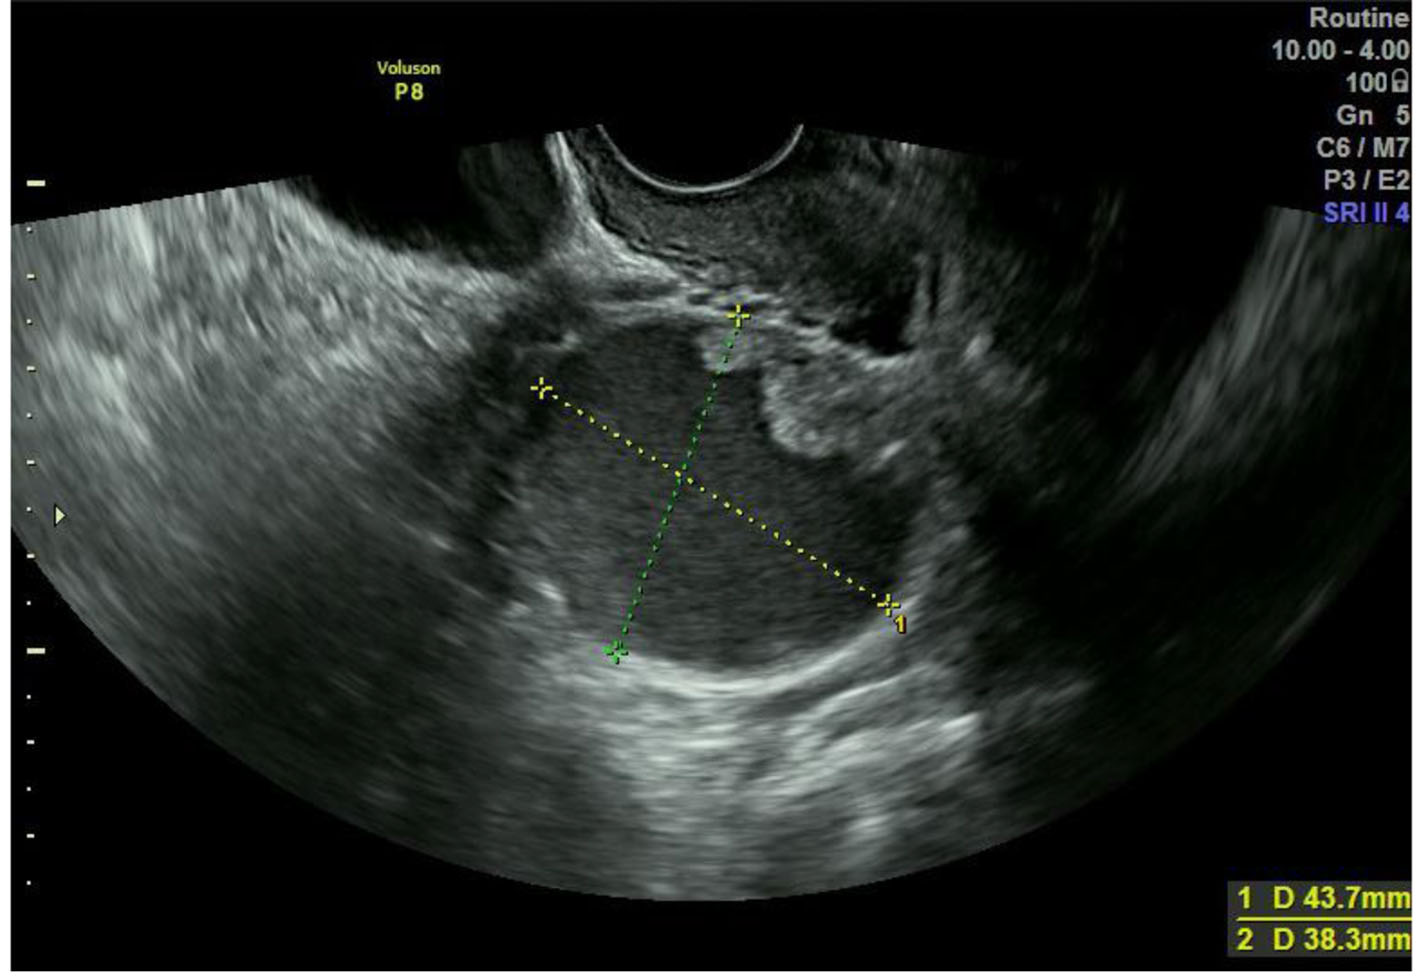

The patient was a 50-year-old woman, who was gravida 2, para 1, and premenopausal. She was found to have a left adnexal mass upon gynecological examination and was referred to our hospital. Past history included angina, cholecystectomy, and appendicitis. She had neither vaginal discharge nor abnormal genital bleeding. Papanicolaou smear test results were normal. Transvaginal ultrasonography revealed a left unilocular adnexal mass 4 cm in diameter and magnetic resonance imaging (MRI) showed a solid component with contrast effect at the luminal wall (Figs. 1 and 2). Serum CA125 and CA19-9 were 50.0 and 27.0 U/mL, respectively. No retroperitoneal lymph node swelling or metastasis was detected on chest and abdominal computed tomography. She underwent laparotomy based on a diagnosis of left ovarian carcinoma. There were no ascites or adhesions in the abdominal cavity. The left fallopian tube showed global swelling, while the left ovary was normal; the uterus and right adnexa were also macroscopically normal. Left salpingo-oophorectomy was initially performed, revealing that the left fallopian tube comprised entirely of a unilocular cyst 4 cm in diameter; normal fimbria were observed on its smooth surface (Fig. 3). The lesion contained serous fluid, and a papillary solid component 1 cm in diameter projected on the inner wall. Histopathological examination of the tumor’s frozen section revealed a serous borderline tumor, after which hysterectomy, right salpingo-oophorectomy, and partial omentectomy were performed. No intraperitoneal spreading was detected macroscopically, and peritoneal washing cytology was negative. Final pathological diagnosis was serous borderline tumor of the left fallopian tube, stage IA. The patient did not undergo adjuvant chemotherapy and had no evidence of recurrence 1 year after surgery.

![]() Click for large image | Figure 1. Transvaginal ultrasonography showing a left unilocular adnexal mass. |